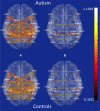

Alterations in interregional neural connectivity have been suggested as a signature of the pathobiology of autism. There have been many reports of functional and anatomical connectivity being altered while individuals with autism are engaged in complex cognitive and social tasks. Although disrupted instantaneous correlation between cortical regions observed from functional MRI is considered to be an explanatory model for autism, the causal influence of a brain area on another (effective connectivity) is a vital link missing in these studies. The current study focuses on addressing this in an fMRI study of Theory-of-Mind (ToM) in 15 high-functioning adolescents and adults with autism and 15 typically developing control participants. Participants viewed a series of comic strip vignettes in the MRI scanner and were asked to choose the most logical end to the story from three alternatives, separately for trials involving physical and intentional causality. The mean time series, extracted from 18 activated regions of interest, were processed using a multivariate autoregressive model (MVAR) to obtain the causality matrices for each of the 30 participants. These causal connectivity weights, along with assessment scores, functional connectivity values, and fractional anisotropy obtained from DTI data for each participant, were submitted to a recursive cluster elimination based support vector machine classifier to determine the accuracy with which the classifier can predict a novel participant's group membership (autism or control). We found a maximum classification accuracy of 95.9% with 19 features which had the highest discriminative ability between the groups. All of the 19 features were effective connectivity paths, indicating that causal information may be critical in discriminating between autism and control groups. These effective connectivity paths were also found to be significantly greater in controls as compared to ASD participants and consisted predominantly of outputs from the fusiform face area and middle temporal gyrus indicating impaired connectivity in ASD participants, particularly in the social brain areas. These findings collectively point toward the fact that alterations in causal connectivity in the brain in ASD could serve as a potential non-invasive neuroimaging signature for autism.